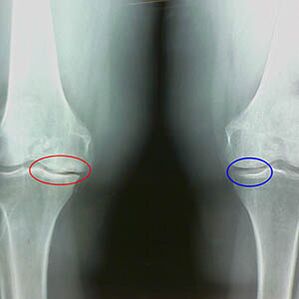

La détermination du degré d'arthrose se produit par la rayure xrévélant la participation au processus pathologique des structures osseuses. Leur changement indique que le système musculaire est dans un déséquilibre depuis 5 à 10 ans. En règle générale, les gens Pendant plusieurs années, ils éprouvent des douleurs douloureuses.

Au premier stade de l'arthrose, qui est détecté par accident, une légère augmentation des éperons osseuses se produit. Les croissances apparaissent dans les lieux de la plus grande instabilité de l'articulation. En règle générale, les patients éprouvent rarement de la douleur ou de l'inconfort pendant le mouvement.

La deuxième étape de l'arthrose est considérée comme facile. La radiographie révèle des éperons osseux importants, mais le cartilage n'est pas affecté. La quantité de liquide synovial est réduite, mais les symptômes de la douleur apparaissent après une longue marche et une course, une raideur dans l'articulation et les douleurs lors de la flexion et de la position sur les genoux.

Les premières caractéristiques des rayons X de la deuxième étape de l'arthrose du genou:

- Les bords pointus des tubercules intermingés sur le tibia, où le ligament en forme de croix est attaché;

- rétrécissement de l'écart articulaire du côté médial;

- Les bords pointus des condyles des os sur les côtés médiaux, moins souvent en latérale - selon le développement du valgus ou de la déformation articulaire variale.

Pour la deuxième étape de Larsen Le rétrécissement de l'écart articulaire de plus de 50% est caractéristique, mais cela ne peut être vérifié que dans la dynamique ou la comparaison avec un joint différent.

La radiographie montre la présence d'ostéophytes, un changement dans l'espace entre les os fémoraux et le tibia, ce qui indique la perte de cartilage dans le genou. Parfois, le rayon X des articulations du genou montre des signes importants d'usure du cartilage, mais les patients ne ressentent pas de douleur significative.Au contraire, l'arthrose de la première étape peut perturber la fonction du genou, puisque la cause de la douleur est les muscles hypotoniques.